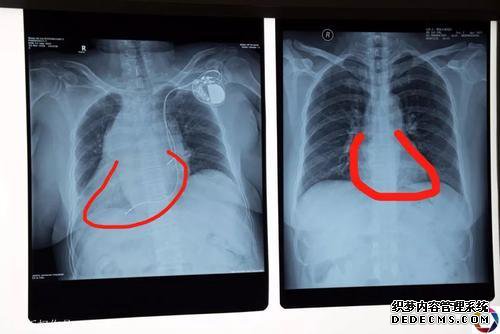

李建伟指出,“镜子里的人”如果是畸形性质的人,即净投资,即净解剖学的人,其数目很少,那是罕见的。,肺,diaphragm肌,肝,脾,胃,肠等。

就像一个普通的人看着镜子,国家是人类的对立面,医学教育被称为“镜子里的人”。